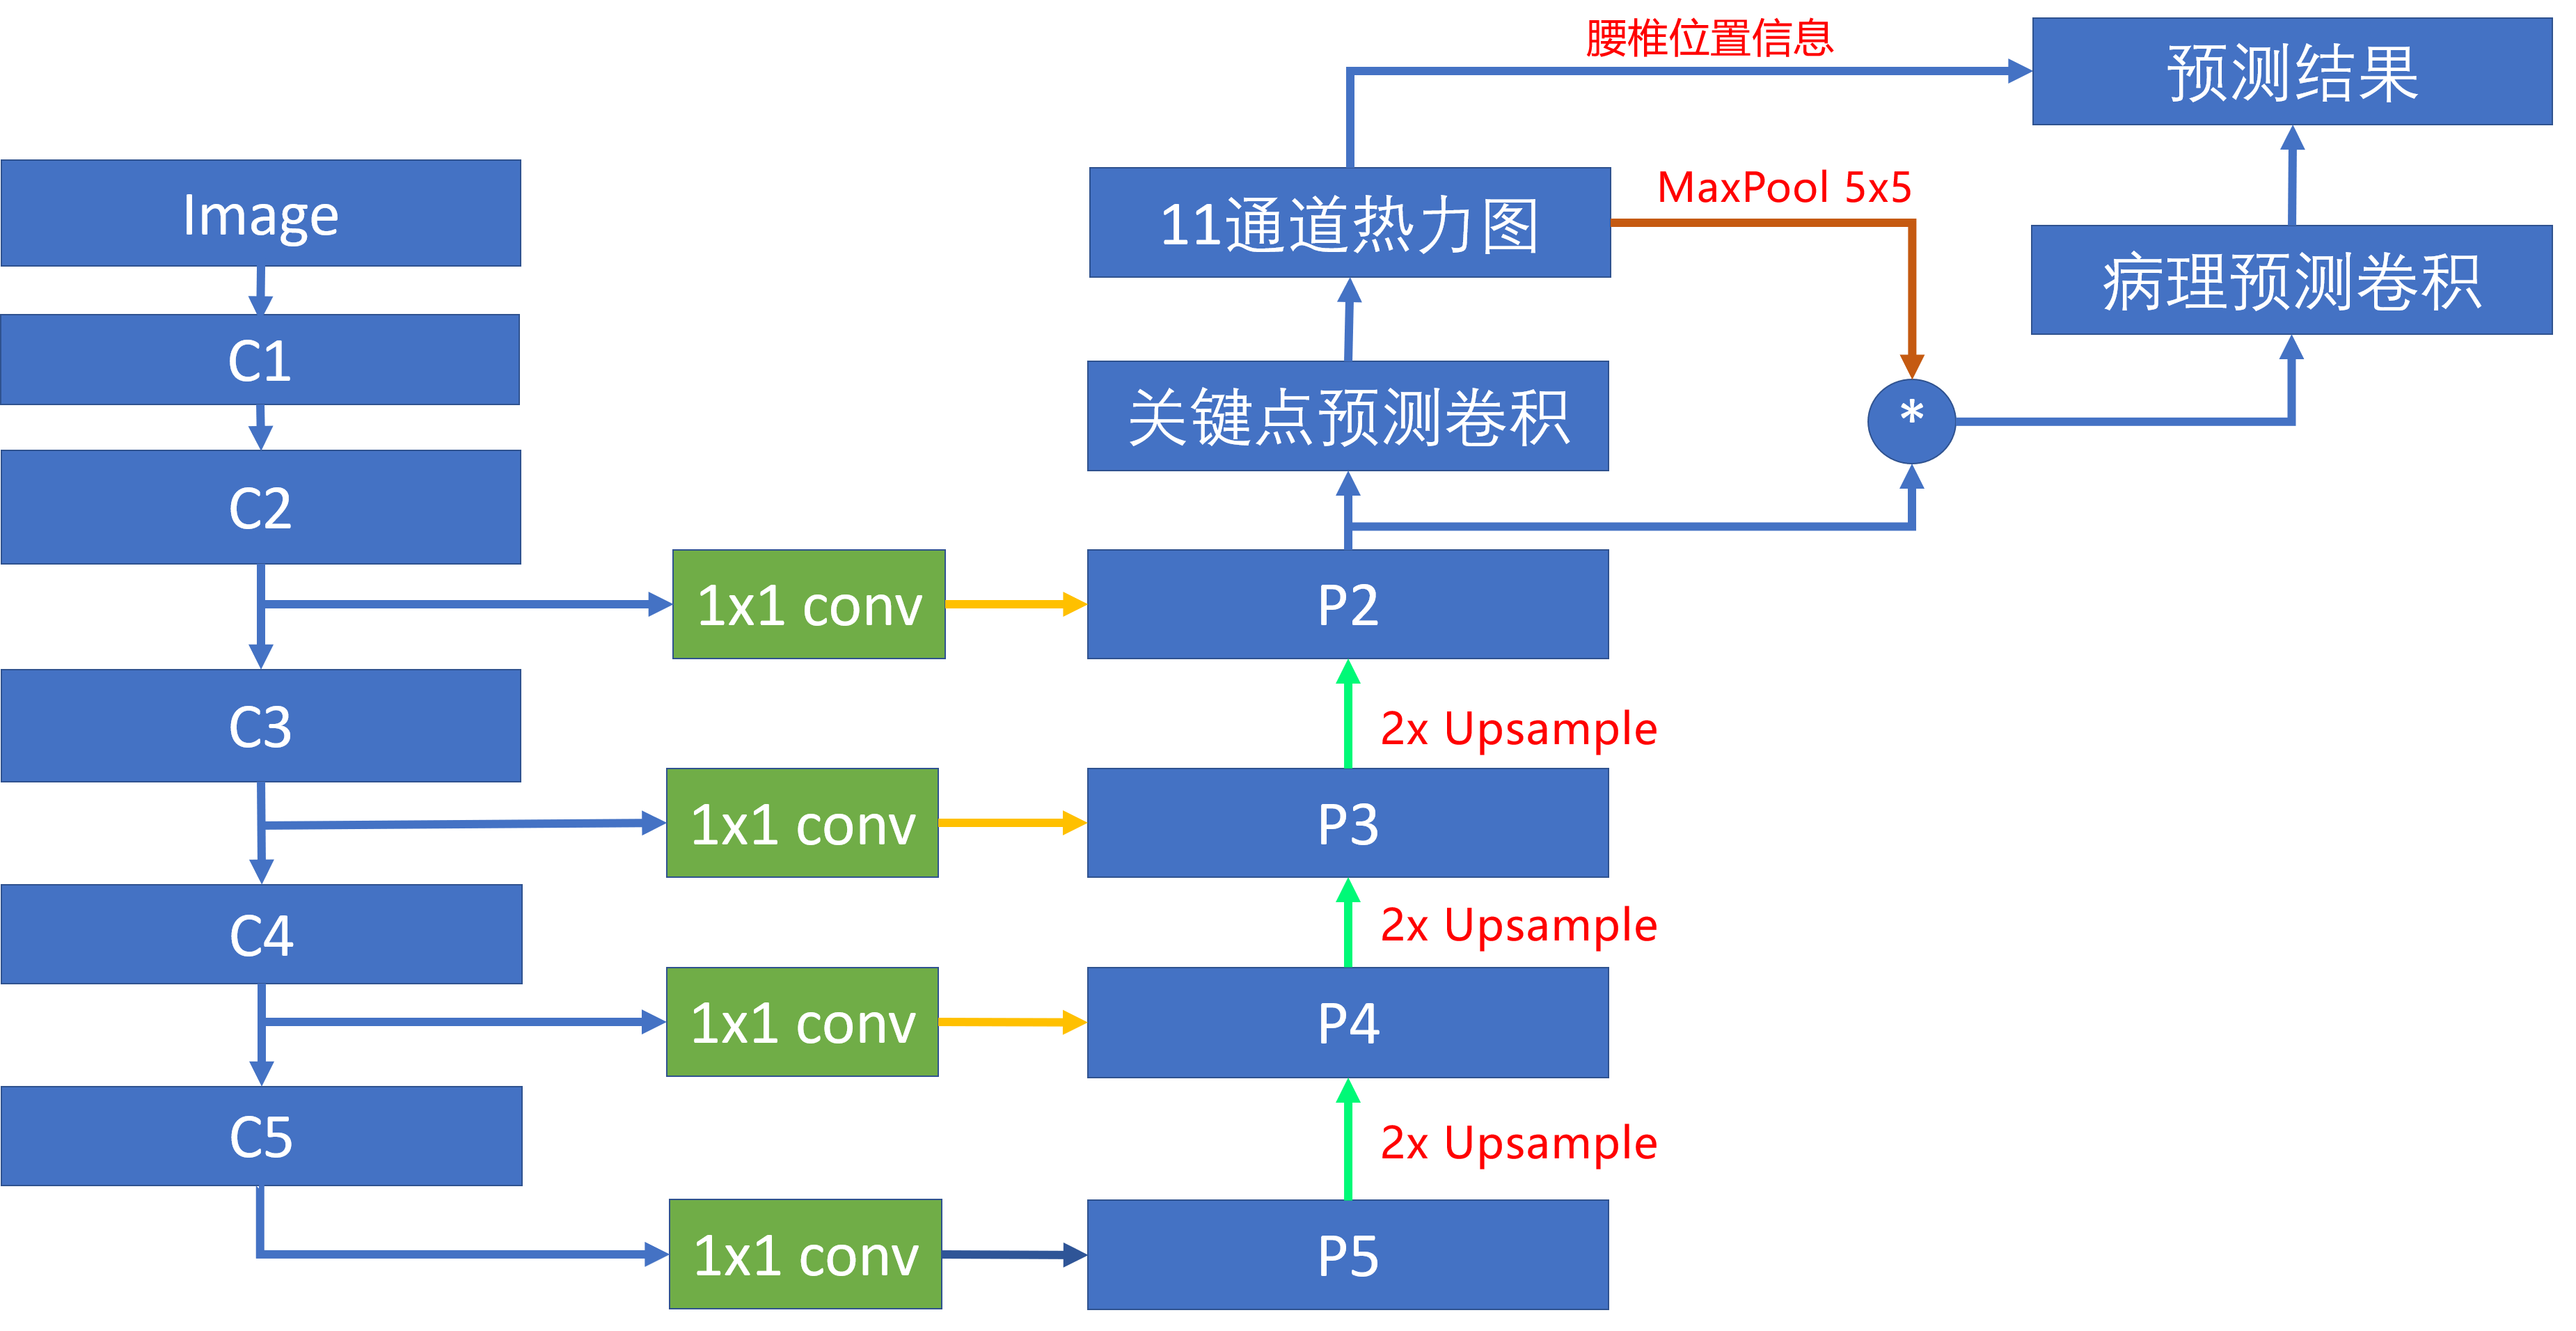

腰椎定位模型使用了FPN(特征金字塔)网络结构,C1-C5为骨干网络,负责提取图像的语义特征,P5-P2将骨干网络的语义特征进行逐级放大,最终得到一个相比原图4倍下采样的关键点的热力图。同时在每个特征放大阶段,使用跳级连接将不同层级的特征进行融合,让特征包含轮廓、边缘信息。

在得到腰椎关键点热力图之后,我们对每个关键点的热力图进行一个5x5的maxpool,扩大热力图关键点区域的面积。然后将每个热力图和前端模块的特征相乘,得到11个不同位置的融合后的特征图。将这些融合后的特征送入分类器中就可以得到腰椎对应的病理类别,整个过程示意图如图。